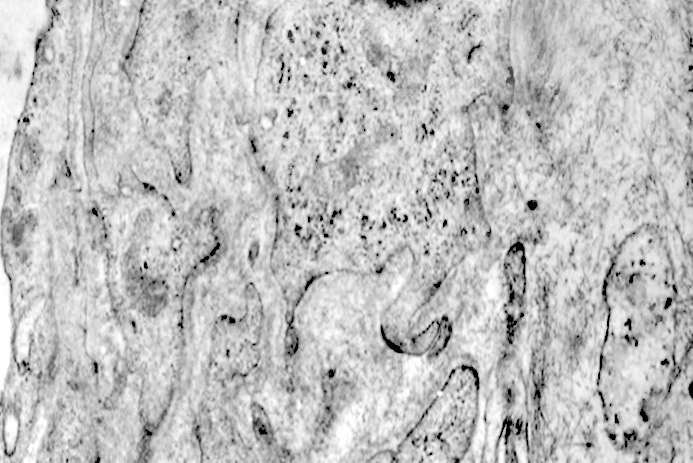

I focolai di macroautofagia possono essere presenti in zone diverse del citoplasma. La loro microstruttura di base è costituita da una area vacuolare demarcata da una membrana a doppio strato; l’area cava è occupata per quote variabili da materiale amorfo,da aggregati filamentosi,da frammenti di organuli,da gruppi granulosi, il tutto in diversi stati di conservazione. Questi focolai macroautofagici appaiono come strutture avulse dalle mutevoli condizioni bio-morfologiche del citoplasma nel quale si sono formate. E’ frequente il riscontro di cellule di aspetto cribroso per la esistenza di micro vacuoli scavati nel citosol e per la dilatazione delle cisterne del reticolo endoplasmico contengano nel citosol una formazione macroautofagica occupata in parte da materiale amorfo e filamentoso.

Non mancano elementi cellulari,forniti di un citosol contenente solo ribosomi liberi, rare strutture reticolo endoplasmatiche in via di disgregazione e molto materiale amorfo, essere occupati da un focolaio di macroautofagia con aggregati di filamenti.

Sono repertabili anche cellule meningoteliali ben strutturate e ricche di organuli marcate da un focolaio di autofagia contenente frammenti di substrutture e materiale filamentoso.